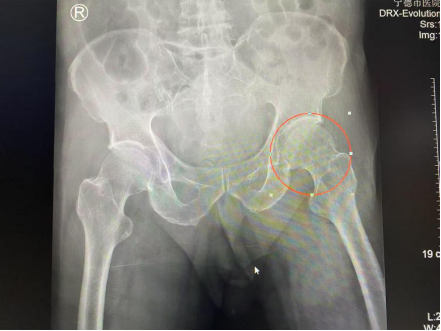

93岁高龄的张大爷(化名)在家不慎跌倒后,辗转来到我院。我院关节与运动医学科与上海市第一人民医院陈疾杵名医工作室联动,远程会诊,制定入院后快速诊疗流程。关节与运动医学科主任医师林久灶、柯铭锋及副主任医师董乃健医疗组迅速响应,即刻启动老年髋部骨折绿色通道,快速完成包括心电图、血生化、肺部CT、心脏彩超等在内的各项检查。考虑到老人本身有岁合并冠心病、心脏支架植入等基础疾病,在报告结果出来后24小时内邀请心内科、麻醉科专家迅速全面评估,进行术前多学科会诊,为患者制定个性化围手术期处理方案。

2月6日,林久灶医疗团队为张大爷实施人工股骨头置换及大粗隆骨折固定手术。术后第1天,老人即可床边坐起,在助行器辅助及家属搀扶下可下地行走;术后第4天,老人自己能下床用助行器行走。目前恢复顺利。